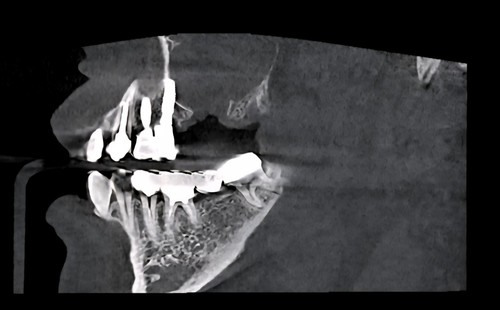

저희 치과에 오신 거는 발치한 날로부터 약 3주가 지난 상태로 오셨는데 발치한 치과에서는 한달이 안 되었기 때문에 더 기다려 볼 것을 권유 받으셨었습니다. 그런데 환자분이 제가 구강상악동누공에 대하여 작성한 포스팅을 보시고 저희 치과를 방문하시게 되었습니다. 보통 발치한지 3주가 되면 구강상악동천공의 단계를 지나서 구강상악동누공의 상태로 발전하게 됩니다. 내원 당시에 찍은 시티에서 10mm 이상의 천공이 확인 되었고 막아 놓았던 비흡수성 차례막을 제거하니 자연 치유될 정도의 천공이 아닌 걸로 확인하고 상악동누공폐쇄술을 시행하기로 하였습니다.